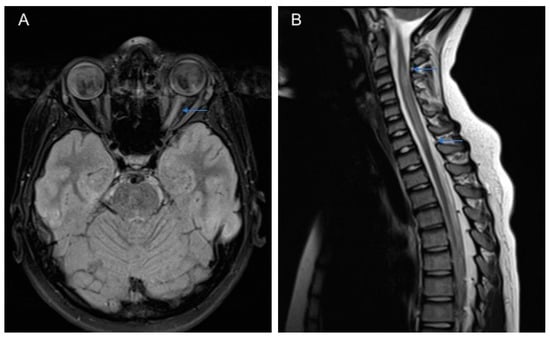

4. Clinical Features and Diagnostic Criteria

| MRI | magnetic resonance imaging |